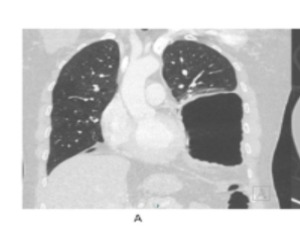

Mechanisms of cardiovascular injuries in SARS-CoV-2 infection

COVID-19 mainly affects the respiratory system; however, cardiovascular complication is not uncommon. Given the high mortality of COVID-19, it is mandatory to understand the pathogenesis and the mechanism of how it attacks the cardiovascular system. Pre-existing cardiovascular diseases have shown higher morbidity and mortality among COVID-19 patients.

Int J Cardiol Cardiovasc Dis, 2022, Volume Volume 2, Issue Issue 1, p1-5 | DOI: 10.46439/cardiology.2.017